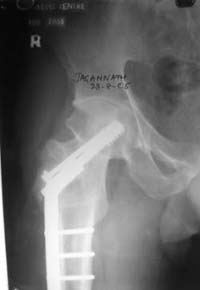

Нелеченный перелом шейки бедра / Neglected femoral neck #

Глубокоуважаемые коллеги,Вчера обратился мужчина 31 г. Травма 2 месяца назад, лечился в одном из городов области. Был не самый тяжелый перелом таза, который проведен консервативно. С ним и связывали невозможность поднять ногу.

Однако на сегодняшнем снимке обнаружился перелом шейки бедра. Больной уже ходитс частичной нагрузкой. Учитывая срок и картину на снимке, что предпринять? У нас предложены варианты 1)не оперировать, 2)закрыто 2 спонгиозных винта, 3)вальгизирующая остеотомия. Эндопротез как-то даже в список включать пока не хочется. Какие есть соображения? Что из перечисленного или что-то другое выбрать и почему? Заранее спасибо.

Dear colleagues,A male 31 years old treated elsewhere after not severe pelvic fracture, was managed non operatively. So the injury looked as a reason of his inability to elevate the leg. However at the recent x-rays the neck fractire was found. The patient already has been walking with partial weight-bearing.Looking at the x-rays and the time since the injury, what is the optimal treatment for now? We discussed 1)leave as is, 2)2 cancellows screws as is, 3)valgus osteotomy. Total hip replacement looks unnecessary yet.What is your opinion? Which option from the listed or something else should be preferred and why?THX in advance.